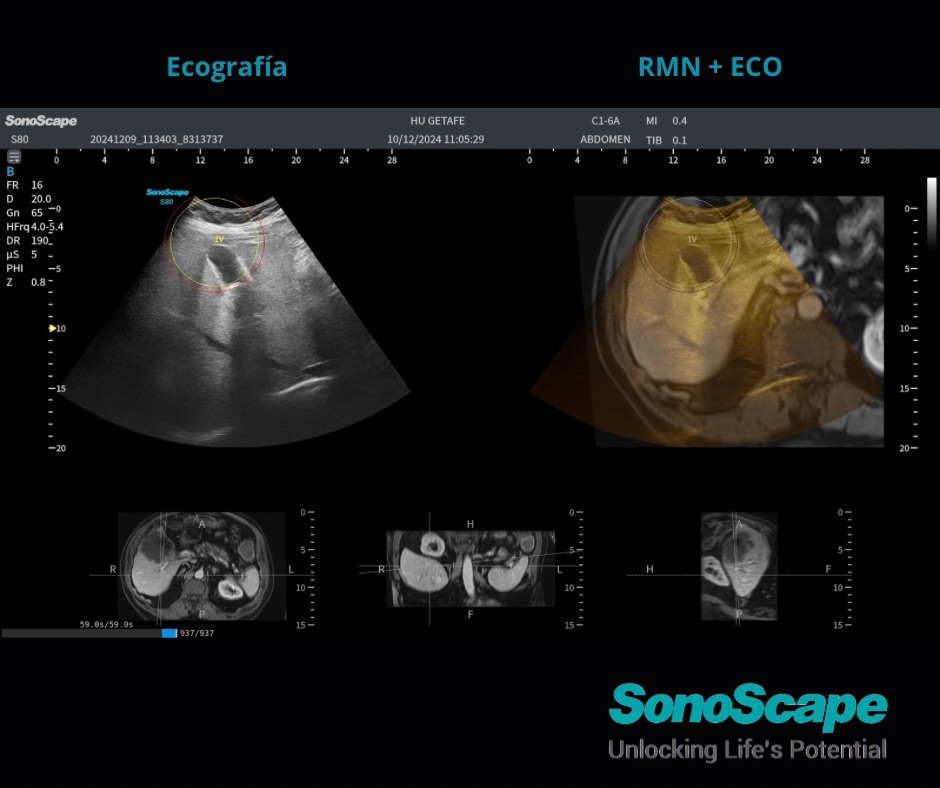

La fusión ecográfica consiste en superponer o alinear la imagen en vivo del ecógrafo con imágenes DICOM previamente adquiridas por otras modalidades. Esto se hace mediante un sistema de navegación que sincroniza los dos conjuntos de imágenes utilizando referencias anatómicas o sensores de posicionamiento.

Mejorar la precisión diagnóstica y la orientación durante procedimientos intervencionistas, especialmente en lesiones difíciles de ver solo con ecografía (por ejemplo, lesiones hepáticas pequeñas o profundas).

Se cargan las imágenes previas (TC, RM) en el ecógrafo. Se utiliza un sistema de navegación (óptico o electromagnético) que localiza en el espacio la posición exacta de la sonda ecográfica. Se alinean los puntos anatómicos clave para sincronizar ambas imágenes. La imagen ecográfica se muestra sobre la imagen de TC/RM en tiempo real.